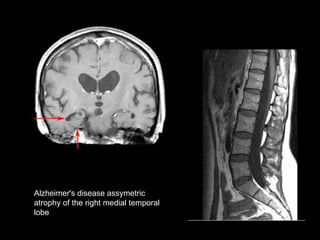

Alzheimer's disease   assymetric  atrophy of the right medial temporal  lobe